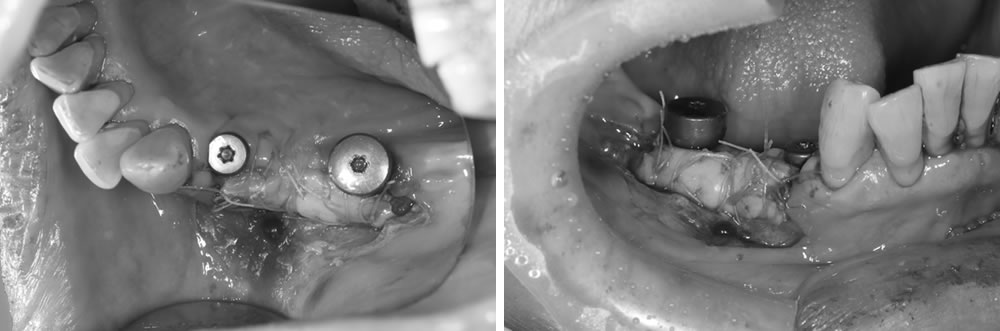

インプラント埋入手術の実施

治療後の経過

FGG(遊離歯肉移植術)の実施